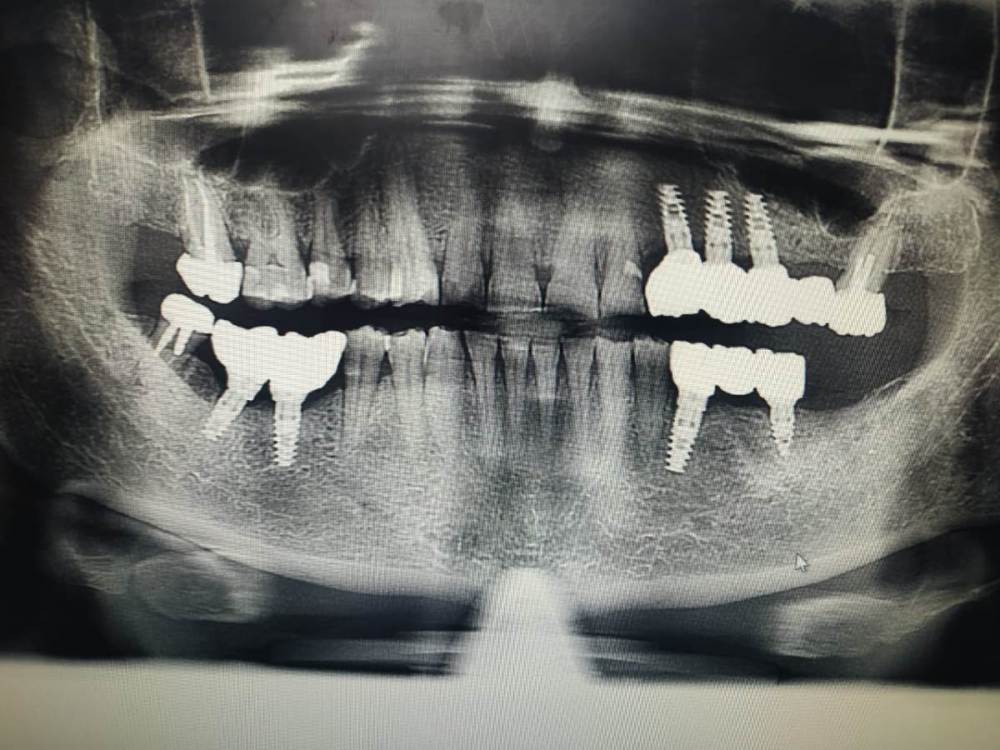

kuziy12 Опубликовано 2 ноября, 2020 Поделиться Опубликовано 2 ноября, 2020 Имплантация с синус лифтингом. Беда с позицией 2.3. Коронки на cad\cam, наносил розовую керамику и красил все сам. Сваливать не на кого) До: После имплантации: Формики: Десна: Постоянная конструкция: Улыбка: 3 Ссылка на комментарий

kuziy12 Опубликовано 3 ноября, 2020 Автор Поделиться Опубликовано 3 ноября, 2020 Шаблончики делайте)Начальству говорю - покупайте КТ. Не хотят гады. 2.6 консольный получился?да Это Вы уже импланты ставите? Умничка!А что за система, небось Ирис? MIS SEVEN Ссылка на комментарий